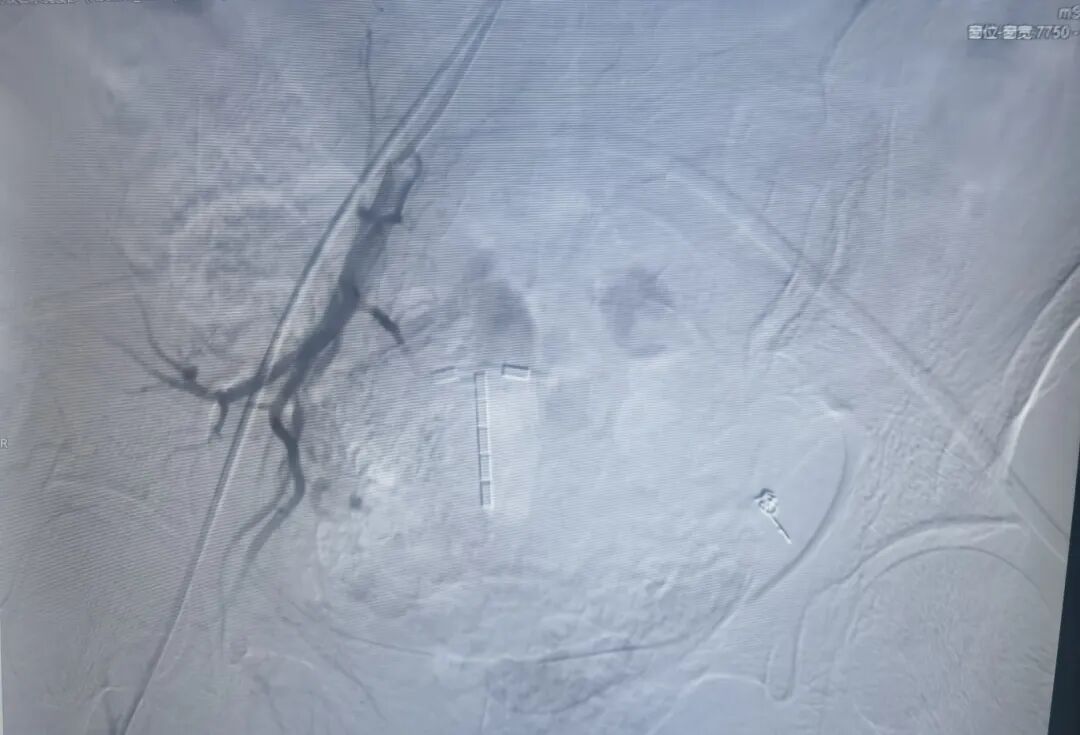

右侧子宫动脉栓塞术后